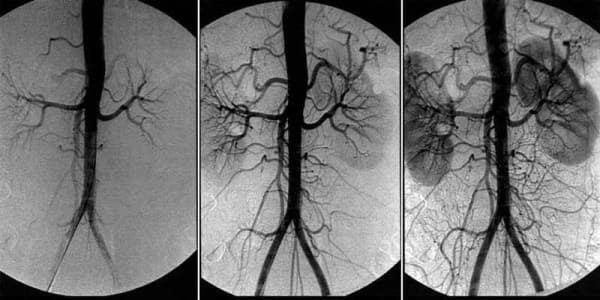

Нарушение на кръвообращението в мозъка — как да разпознаем предстоящата беда и да се предпазим от опасни последици.

Нарушение на кръвообращението в мозъка това е патологично състояние, при което тонусът на кръвоносните съдове и нормалното функциониране на мозъчните тъкани са нарушени. В тази статия можете да прочетете за причините, механизмите и симптомите, при които е време да се задейства алармата. Както и за страховитите усложнения на това коварно заболяване и за съвременния подход към терапията, достъпен за всеки.

В основата на терапията на кръвообращението на мозъчните съдове е почистването на съдовете на цялото тяло от натрупаните замърсители. Холестеролни плаки, кръвни съсиреци и калциева вар.